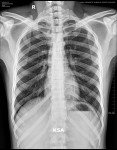

X-RAY INVESTIGATION

CHEST X-RAY Hilar Calcification Lt Side

HIS/HER STATUS : HELD UP

REMARKS : , 45% Risk For X-ray,